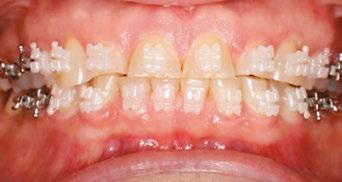

The following is one of our adult orthodontic cases treated with Ormco’s Symetri brackets.

Case report

A 49-year-old female presented for an initial orthodontic exam with the chief complaint of bruxing and excessive wear on her teeth, especially the anterior. She was aware of the loss of tooth height and discussed restoration plans with her dentist. She had no history of previous orthodontic treatment and was wearing a maxillary flat-plane occlusal guard from her dentist. She was aware of daytime clenching and grinding but did not report any TMJ pain, clicking, or popping. Maximum opening and range of motion were within normal limits. Cephalometric

Figures 1-5: Initial dental photos

analysis showed that she had a brachycephalic skeletal pattern, but ANB and inter-incisal angles were normal. Occlusal wear in and of itself does not affect patient quality of life,3 but some patients are self-conscious about the appearance of their short, worn teeth, which is the category that this patient fits into. Her chief concern was to improve her dental esthetics.